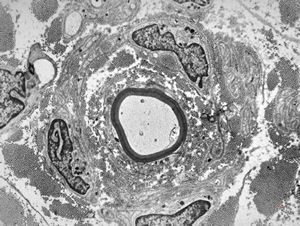

F,23y. | - n.suralis- hypertrophic demyelinizing neuropathy (onion bulbs)